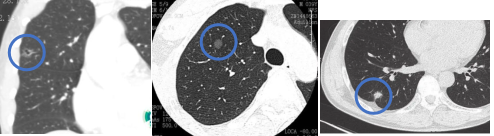

肺结节是指影像学(CT/X线)上表现为直径≤3cm的局灶性、类圆形、密度增高的肺部阴影。随着人们健康意识的提高和检查设备的不断先进,肺结节在健康人群查体中的检出率在50%-60%左右,且呈现年轻化态势,大多数肺结节为良性病灶,只有约3%-5%的肺结节为恶性结节,即肺癌。

高危结节有哪些影像表现

高危结节通常伴随有特征性影像表现,最常见的为毛刺,分叶,血管集束征,胸膜凹陷,空泡征等。具备以上影像表现的结节大多为恶性结节,需重点关注,防止延误病情。